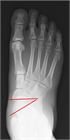

1. 分類は、変形のステージとタイプ分けからなる([1]。ステージは、足変形に可撓性があればⅠ、なければIIとする。変形のタイプはクラスAからクラスEの5つに細分され、クラスは単独あるいは複合することもある(表記例:ⅠA、IIABCIEなど)。(*日本足の外科学会用語委員会による和名)